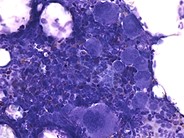

Idiopathic Thrombocytopenic Purpura - 2. Idiopathic Thrombocytopenic Purpura - 4. Immune Thrombocytopenia (ITP): Background, Pathophysiology, Etiology Giant thrombocyte in peripheral blood smear of an ITP patient ... Idiopathic Thrombocytopenic Purpura Smear